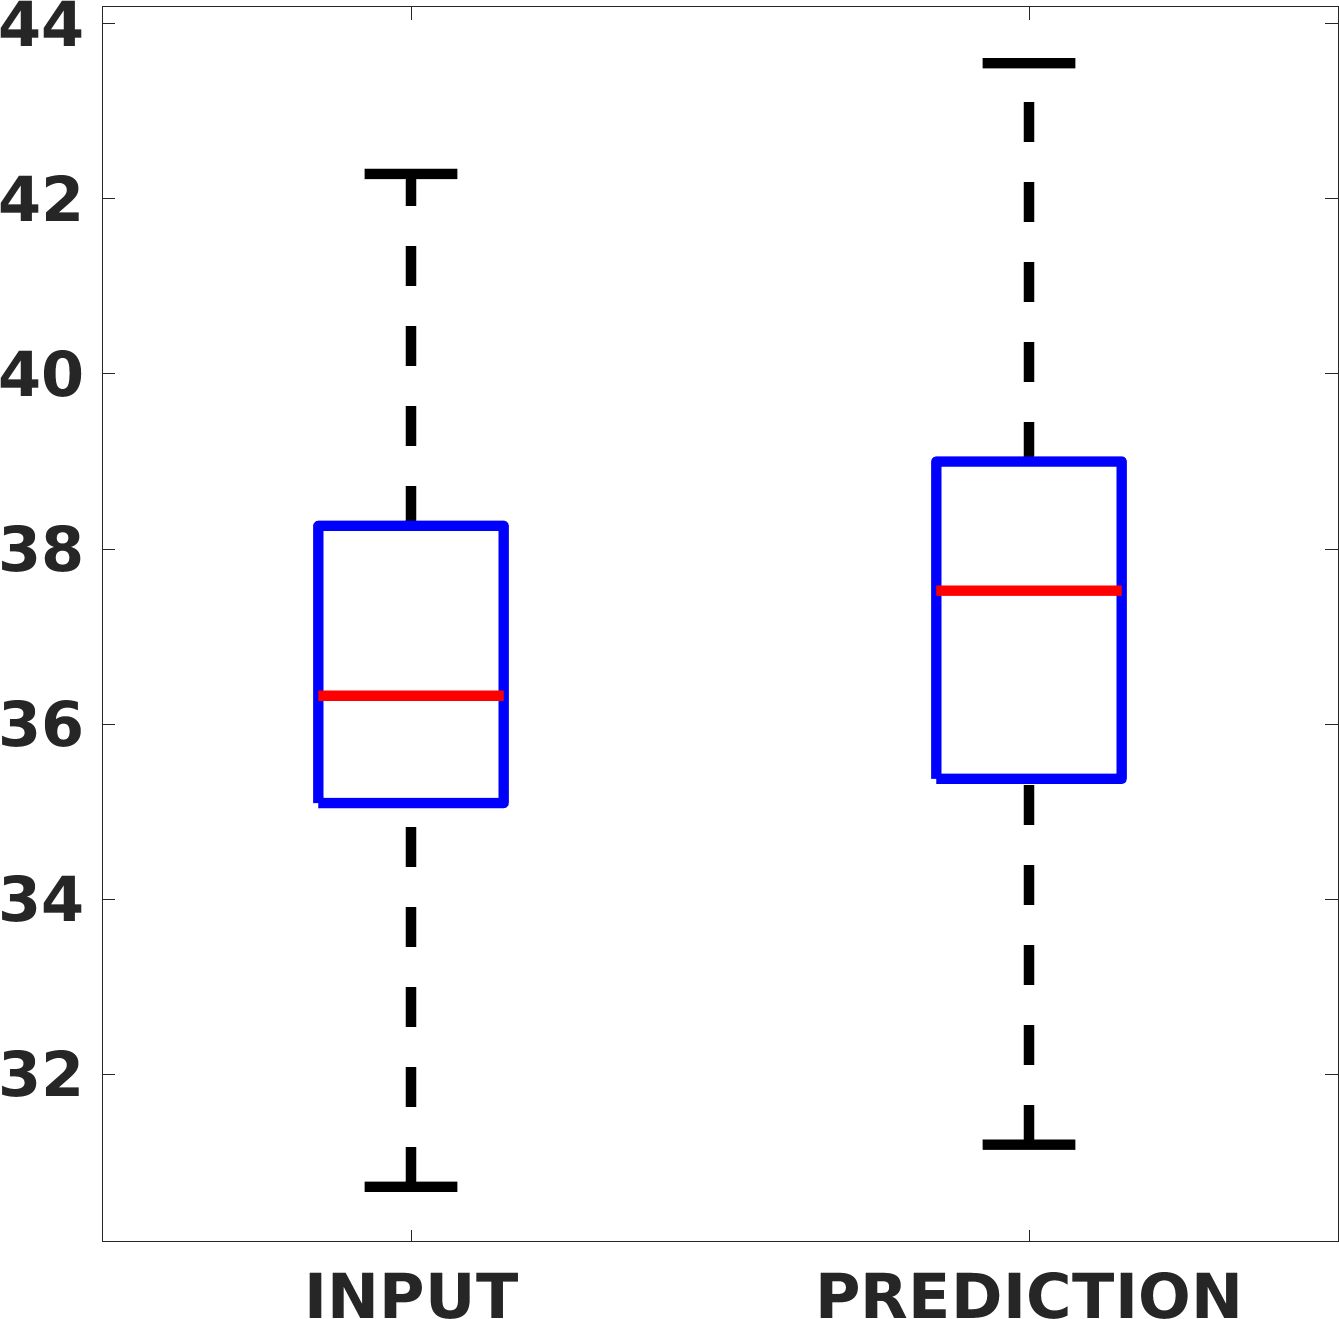

Fig. 17 (left) shows the box plot of the quantitative metrics, comparing the target images with the prediction and the Cubic convolution, respectively. The PSNR metric is computed on a data set of 200 images, belonging to the same district, and with the same up-sampling factor. Analysing the obstetric anatomical district and concerning the corresponding raw images (Fig. 7 (a, left)), the denoising allows the network to significantly improve the results of the up-sampling and the prediction. In particular, comparing the target images with the predicted images, the median PSNR value of obstetric 2X denoised images is 51.8, compared to the median PSNR value of obstetric 2X raw images which is 36.9.

Fig. 17 (right) shows the histogram of the absolute value of the error with respect to the target, of the prediction and Cubic convolution respectively. This result shows that our framework increase of and (2X and 4X, respectively) the number of pixels where the prediction error is lower than 5, which is very similar to the target when visually analysing the images, and improved with respect to the learning framework applied to raw images. According to Fig. 18, our method improves the accuracy of Cubic convolution. For example, the SSIM increases of on cardiac 2X and the MAE increases of on abdominal 4X.